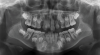

Fig 4. Initial panoramic x-ray.

Figure 4